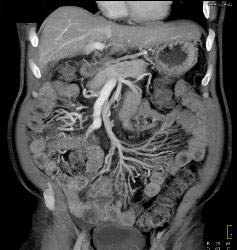

Cirrhosis With Gastric Varices